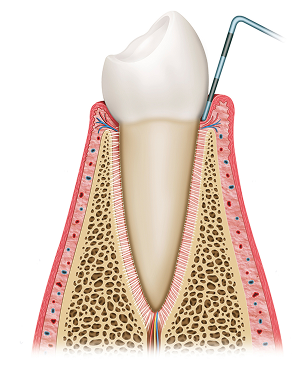

건강한 잇몸

색, 모양

• 담홍색(연분홍)

• 가장자리가 날렵하고 얇음

• 만지면 단단

• 통증, 출혈 거의 없음

• 입냄새 없음

• 정기 스케일링(6개월 간격)

• 바른 양치 습관/치실·치간칫솔

• 금연, 당뇨 관리